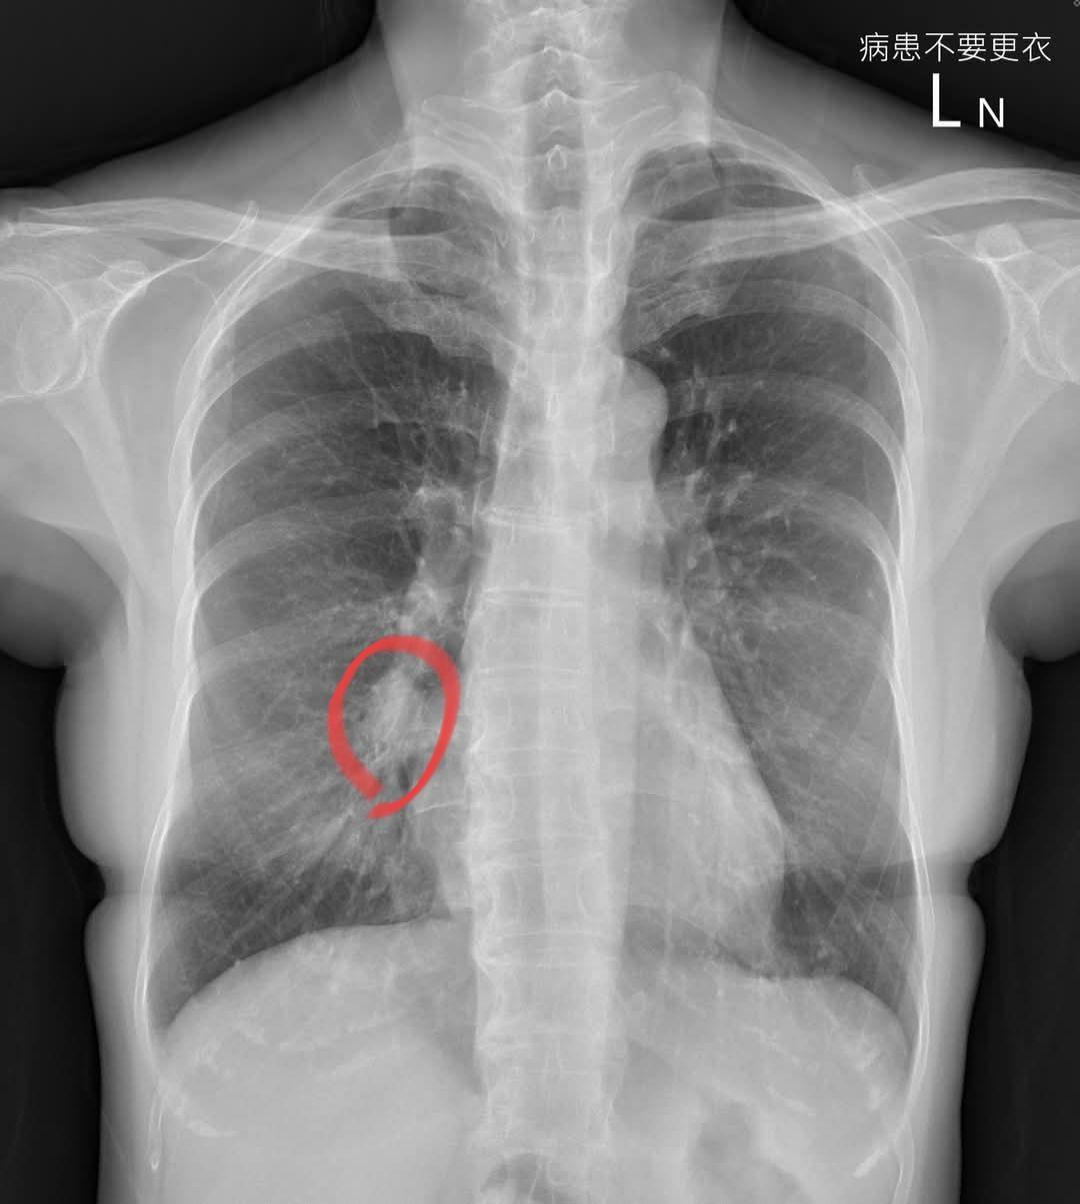

蘇一峰在臉書分享案例,一名60歲不抽菸女性患者,輕微的咳嗽半年多沒好,期間去過其他醫學中心,照X光看了沒事,判斷可能是長新冠,治療後咳嗽還是沒改善。

後來該病患轉至蘇一峰門診,X光一照他看完覺得有問題,「讓大家找看看在哪裡」,於是安排了後續的電腦斷層檢查,發現是3公分的肺癌,大概第二期或三期。